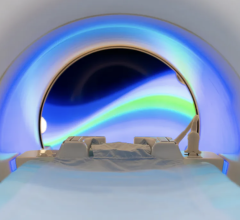

CADstream solutions provide fast, easy and reliable analysis and interpretation of breast and prostate MRI studies. At RSNA, Merge Healthcare will show works-in-progress for its newest CADstream application designed specifically for liver MRI studies.

MRI is a vital imaging tool for the evaluation, assessment and management of the liver. CADstream’s liver application features include automated 3D image registration, segmentation (including whole organ, Couinaud-segments and lesion segmentation), kinetic and diffusion-weighted imaging analysis, patient monitoring comparisons and reporting. With CADstream, clinicians have a solution to automate analysis and standardize interpretation, ultimately achieving higher quality imaging studies, lower costs for radiology practices and improved communication for physicians and patients. Merge CAD will also showcase the latest in CADstream’s breast and prostate applications at RSNA 2009.